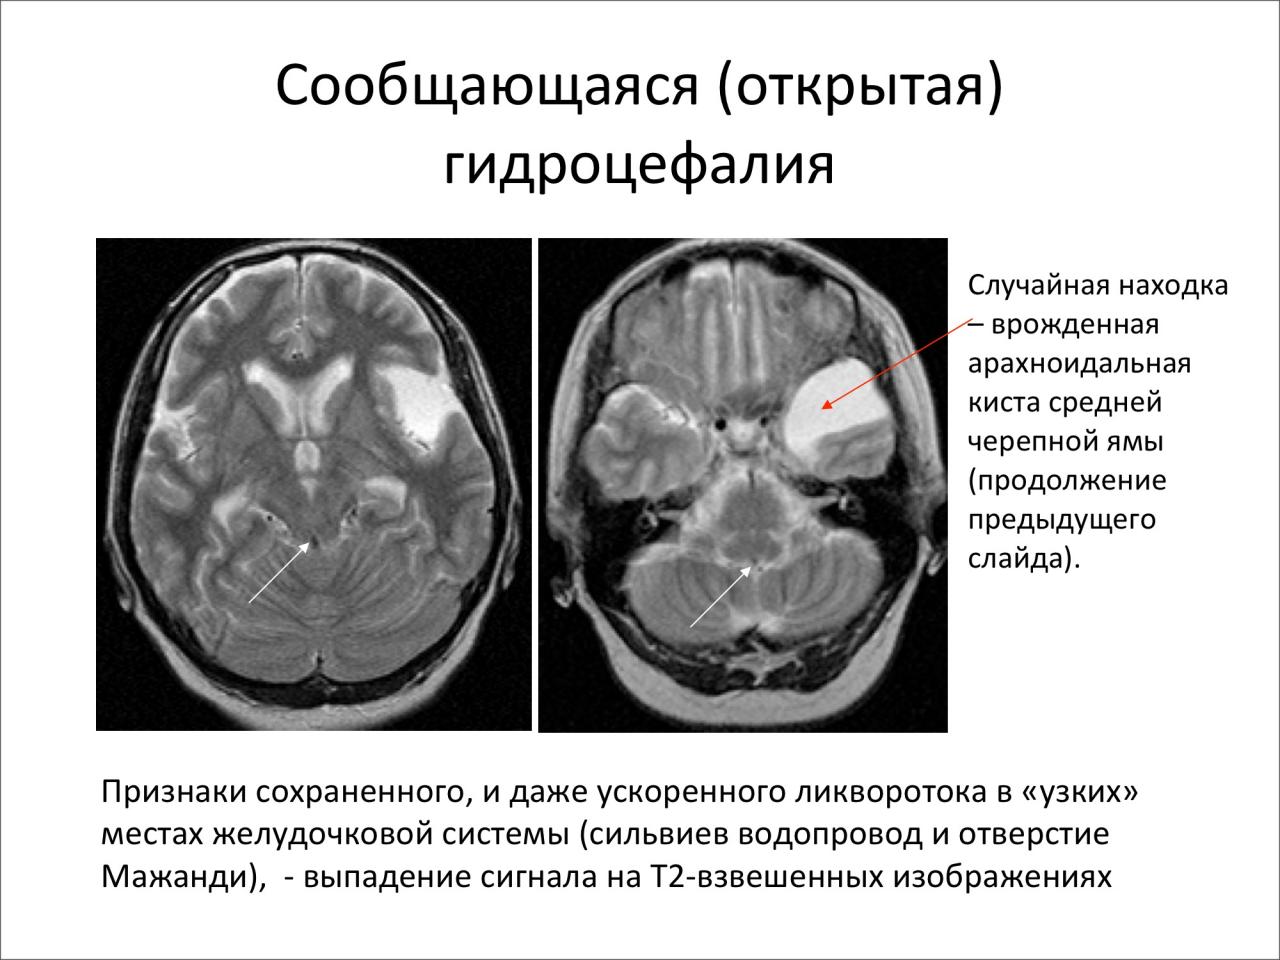

Признаки умеренно выраженной наружная

Признаки умеренно выраженной наружная 113 фото